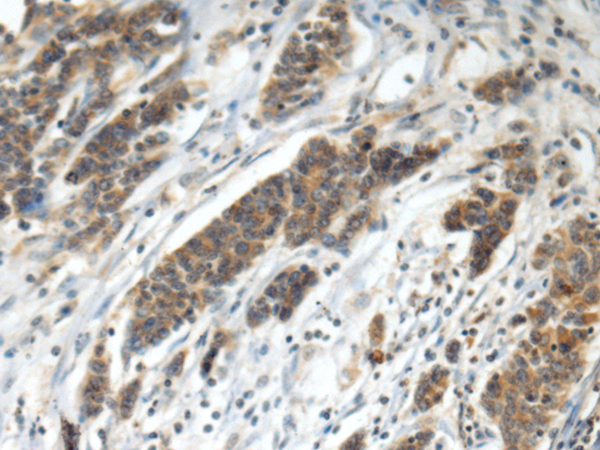

IHC positive control: |

Human colorectal cancer |

IHC Recommend dilution: |

100-300 |